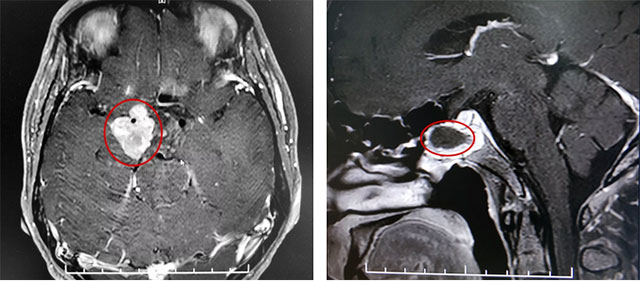

患者蔡先生(化名)因持续头痛、视力下降被查出是垂体无功能巨大腺瘤,肿瘤大小超过3cm。在杭州一家医院做了经蝶窦垂体瘤切除手术后,由于术后肿瘤残余较多,出现头痛情况,视力较术前未见明显改观,左侧视力0.12,右侧视力0.1。后慕名来到上海蓝十字脑科医院。

该巨大垂体腺瘤患者鞍上区域残余肿瘤偏向右侧,只能通过开颅手术切除。

在充分准备并征得家属同意后,李士其教授在吴治群博士、黄秀夫医生协助下为患者行开颅手术,经翼点入路将残余约2.5cm*2cm*2cm大小肿瘤切除。